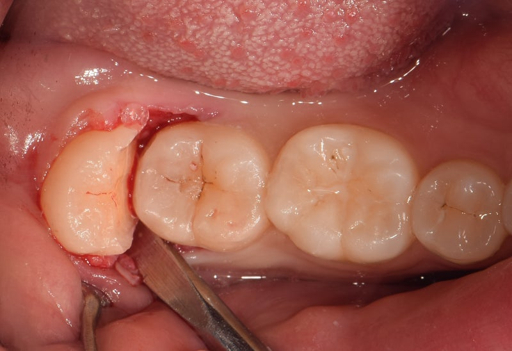

1. 피가 멈추지 않을 때 (지혈법)

발치 후 1~2일간 침에 피가 섞여 나오는 것은 정상이나,

거즈 재압박 (가장 중요):

깨끗한 멸균 거즈를 두껍게 접어

발치 부위에 정확히 올리고

1~2시간 동안 꽉 물고 계세요.